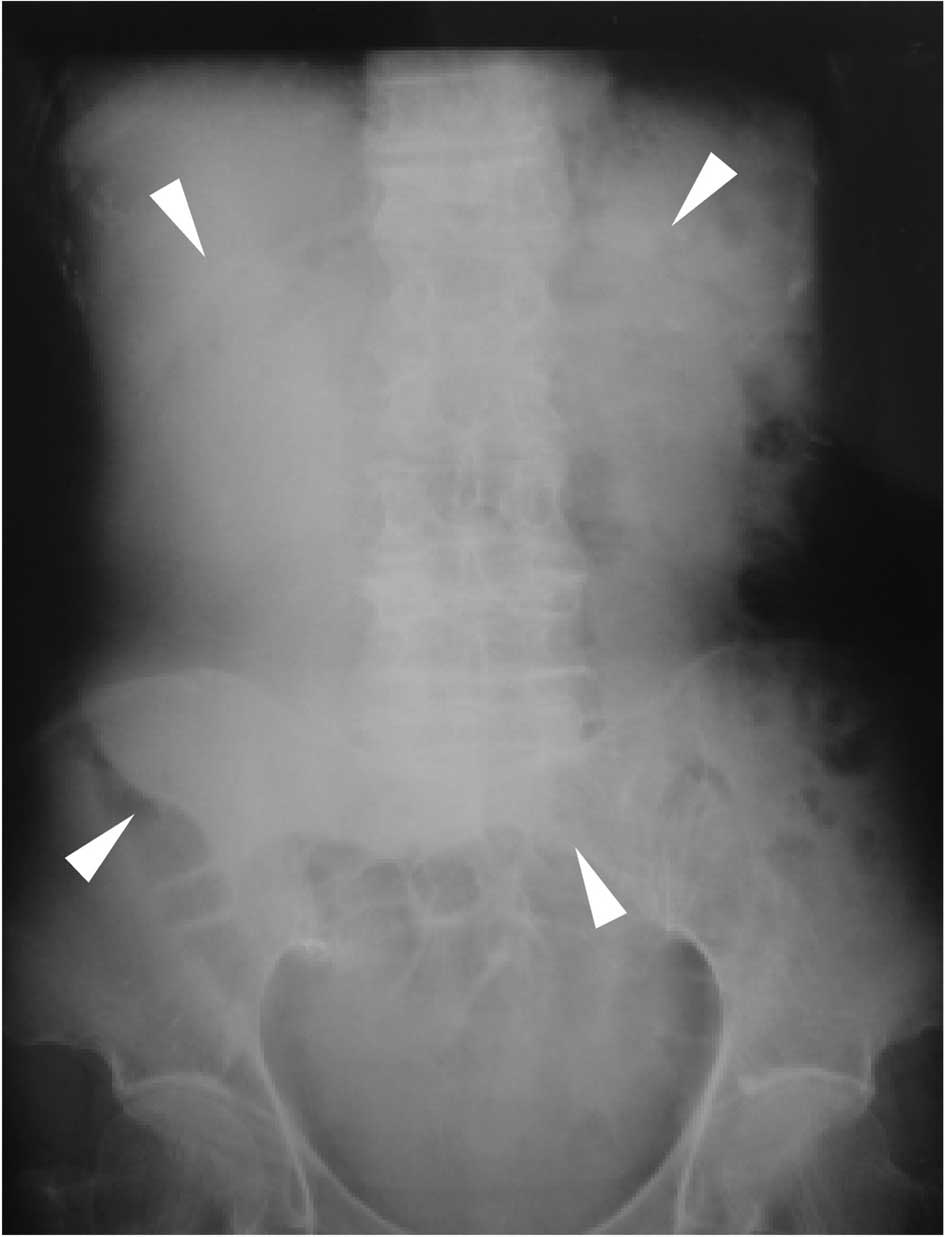

A 79-year-old Japanese female suffering from upper abdominal pain and distention was admitted to our hospital. The patient had previous illness of note nor a family history of disease. A large mass was palpable in the right upper quadrant of the abdomen. The patient’s lactate dehydrogenase was elevated to 413 IU/l (normal range <230), and two serum tumor markers, carcinoembryonic antigen (CEA) and carbohydrate antigen 19-9 (CA19-9), were both elevated at 3.4 ng/ml (normal range <2.5) and 1465.3 U/ml (normal range <37), respectively. Abdominal radiography showed an oval radio-opaque shape of 15 cm in diameter in the right upper abdomen (Fig. 1). Ultrasonography (Fig. 2) and computed tomography (CT) (Fig. 3) revealed the tumor to be a monolocular cyst with an irregular wall thickness of 15 cm in diameter concomitant with a solid mass of 8 cm in diameter around the gallbladder bed, suspected to be a tumor originating from the gallbladder. Endoscopic examinations of the alimentary tract showed no abnormalities. During celiotomy, the tumor with a large pale gray cystic component was identified at the fundus of the gallbladder. The tumor fibrously adhered to the liver, duodenum, and greater omentum, but it appeared to have only partially infiltrated into the transverse colon. A number of small nodules suspected to be tumor dissemination were scattered on the peritoneum. Gallbladder cancer with peritoneal dissemination was diagnosed. Although curative resection for the tumor was impossible, a simple cholecystectomy was performed that included the tumor without systematic lymphadenectomy, and a partial resection of the transverse colon was added due to its tight adhesion by the tumor cyst.

Figure 1

An oval-shaped tumor was suspected upon abdominal radiography.